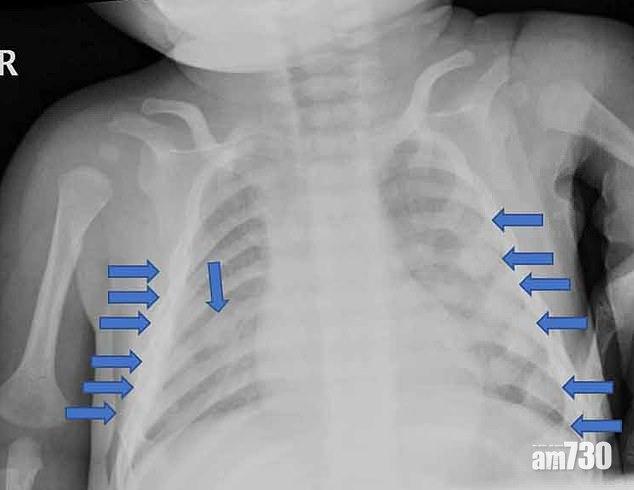

男嬰肋骨多處骨折。(互聯網)

點可以對子女咁殘忍?!英國布賴頓(Brighton)一名4個月大男嬰慘被惡父母家暴,手臂、肋骨、膝蓋、腳踝等全身28處骨折,估計送院前4至6周持續受虐,兒科專家指,從傷勢判斷,男嬰一些骨被人像扭毛巾般扭斷。案發於17年,有家暴案底的男子建卓札克(Adam Jendrzeczak)與女友柯賓絲卡(Aleksandra Kopinska),將4個月大的男嬰送院,報稱他被地毯絆倒而跌斷手臂,但醫生發現男嬰身體多處骨折,明顯由強大外力造成,於是報警,警方以虐兒罪拘捕兩人,兩人其後被裁定16年11月至17年2月期間虐待兒童罪成,案件周一宣判。